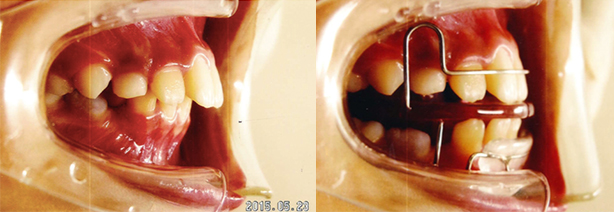

出っ歯(上顎前突)

出っ歯の治療方法は子どもと大人で違います。子供の場合は、あごの成長を止めることで、

バランス良い歯並びに調整します。大人の場合は、歯を移動させることで、出っ歯を改善させます。

-

治療前

-

治療後